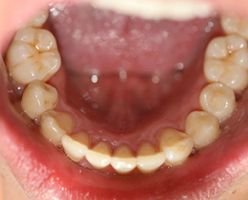

Before

After